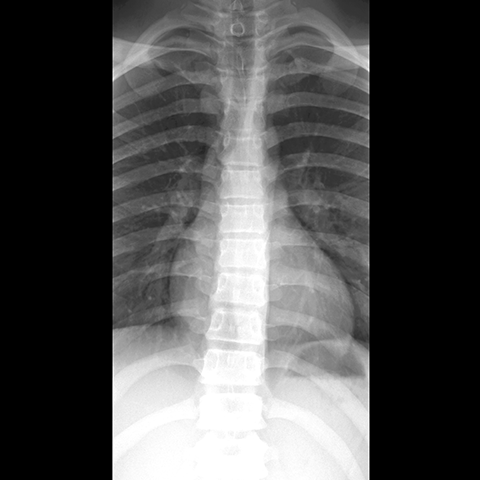

Thoracic Spine, plain film (AP view) [1 of 3]